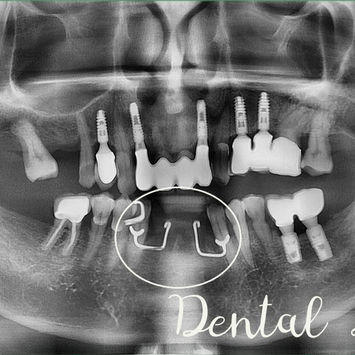

Implant Placement Surgery for Replacement of Missing #41, #42, #31 & #32

Patient presents for implant-supported replacement of missing lower anterior teeth (#41, #42, #31, #32).

Missing #41, #42, #31, #32

Placement of four implants at #41, #42, #31, #32

Four implants placed: 3.0mm × 10.0mm Dentium Slim Line Implants at #41, #42, #31, #32

Post-op CBCT taken

Implants well-aligned; optimal positioning

Bone graft dense and well-packed

Inferior dental nerve not involved